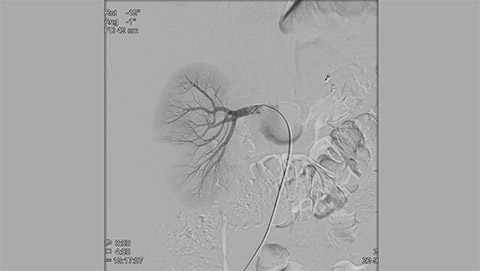

Live 3D MR/CT Roadmap fuses live 2D fluoroscopy on a pre-acquired MR or CT image, which may reveal hidden anomalies and enable real-time motion compensated navigation to support interventional procedures. Live 3D MR/CT Roadmap provides full 3D view for guidance of guidewires, catheters and coils through complex vessel and anatomical structures.

Dynamic 3D Roadmap provides a sustainable 3D roadmap to support interventional procedures. Dynamic 3D Roadmap matches the real-time 2D fluoroscopy images with the 3D-RA reconstruction of the vessel tree. It provides a 3D real-time insight of the advancement of the guide wire, catheter and coils through complex vessel structures. The Unsubtracted 3D Roadmap option reduces subtraction artifacts caused by patient breathing and movements, providing a clear roadmap during abdominal and thoracic interventions.

Live 3D Roadmap allows you to follow the advancement of guidewires, catheters and coils in real-time. It automatically adapts in real-time to changes in C-arm angulation and rotation, table movement, field of view and source-image distance.

High-resolution 3D-RA vascular images or previously acquired 3D segmented MRA or CTA data is registered to the current patient position through a low X-ray dose 3D-RA scan, allowing ‘re-use’ of contrast and X-ray doses.